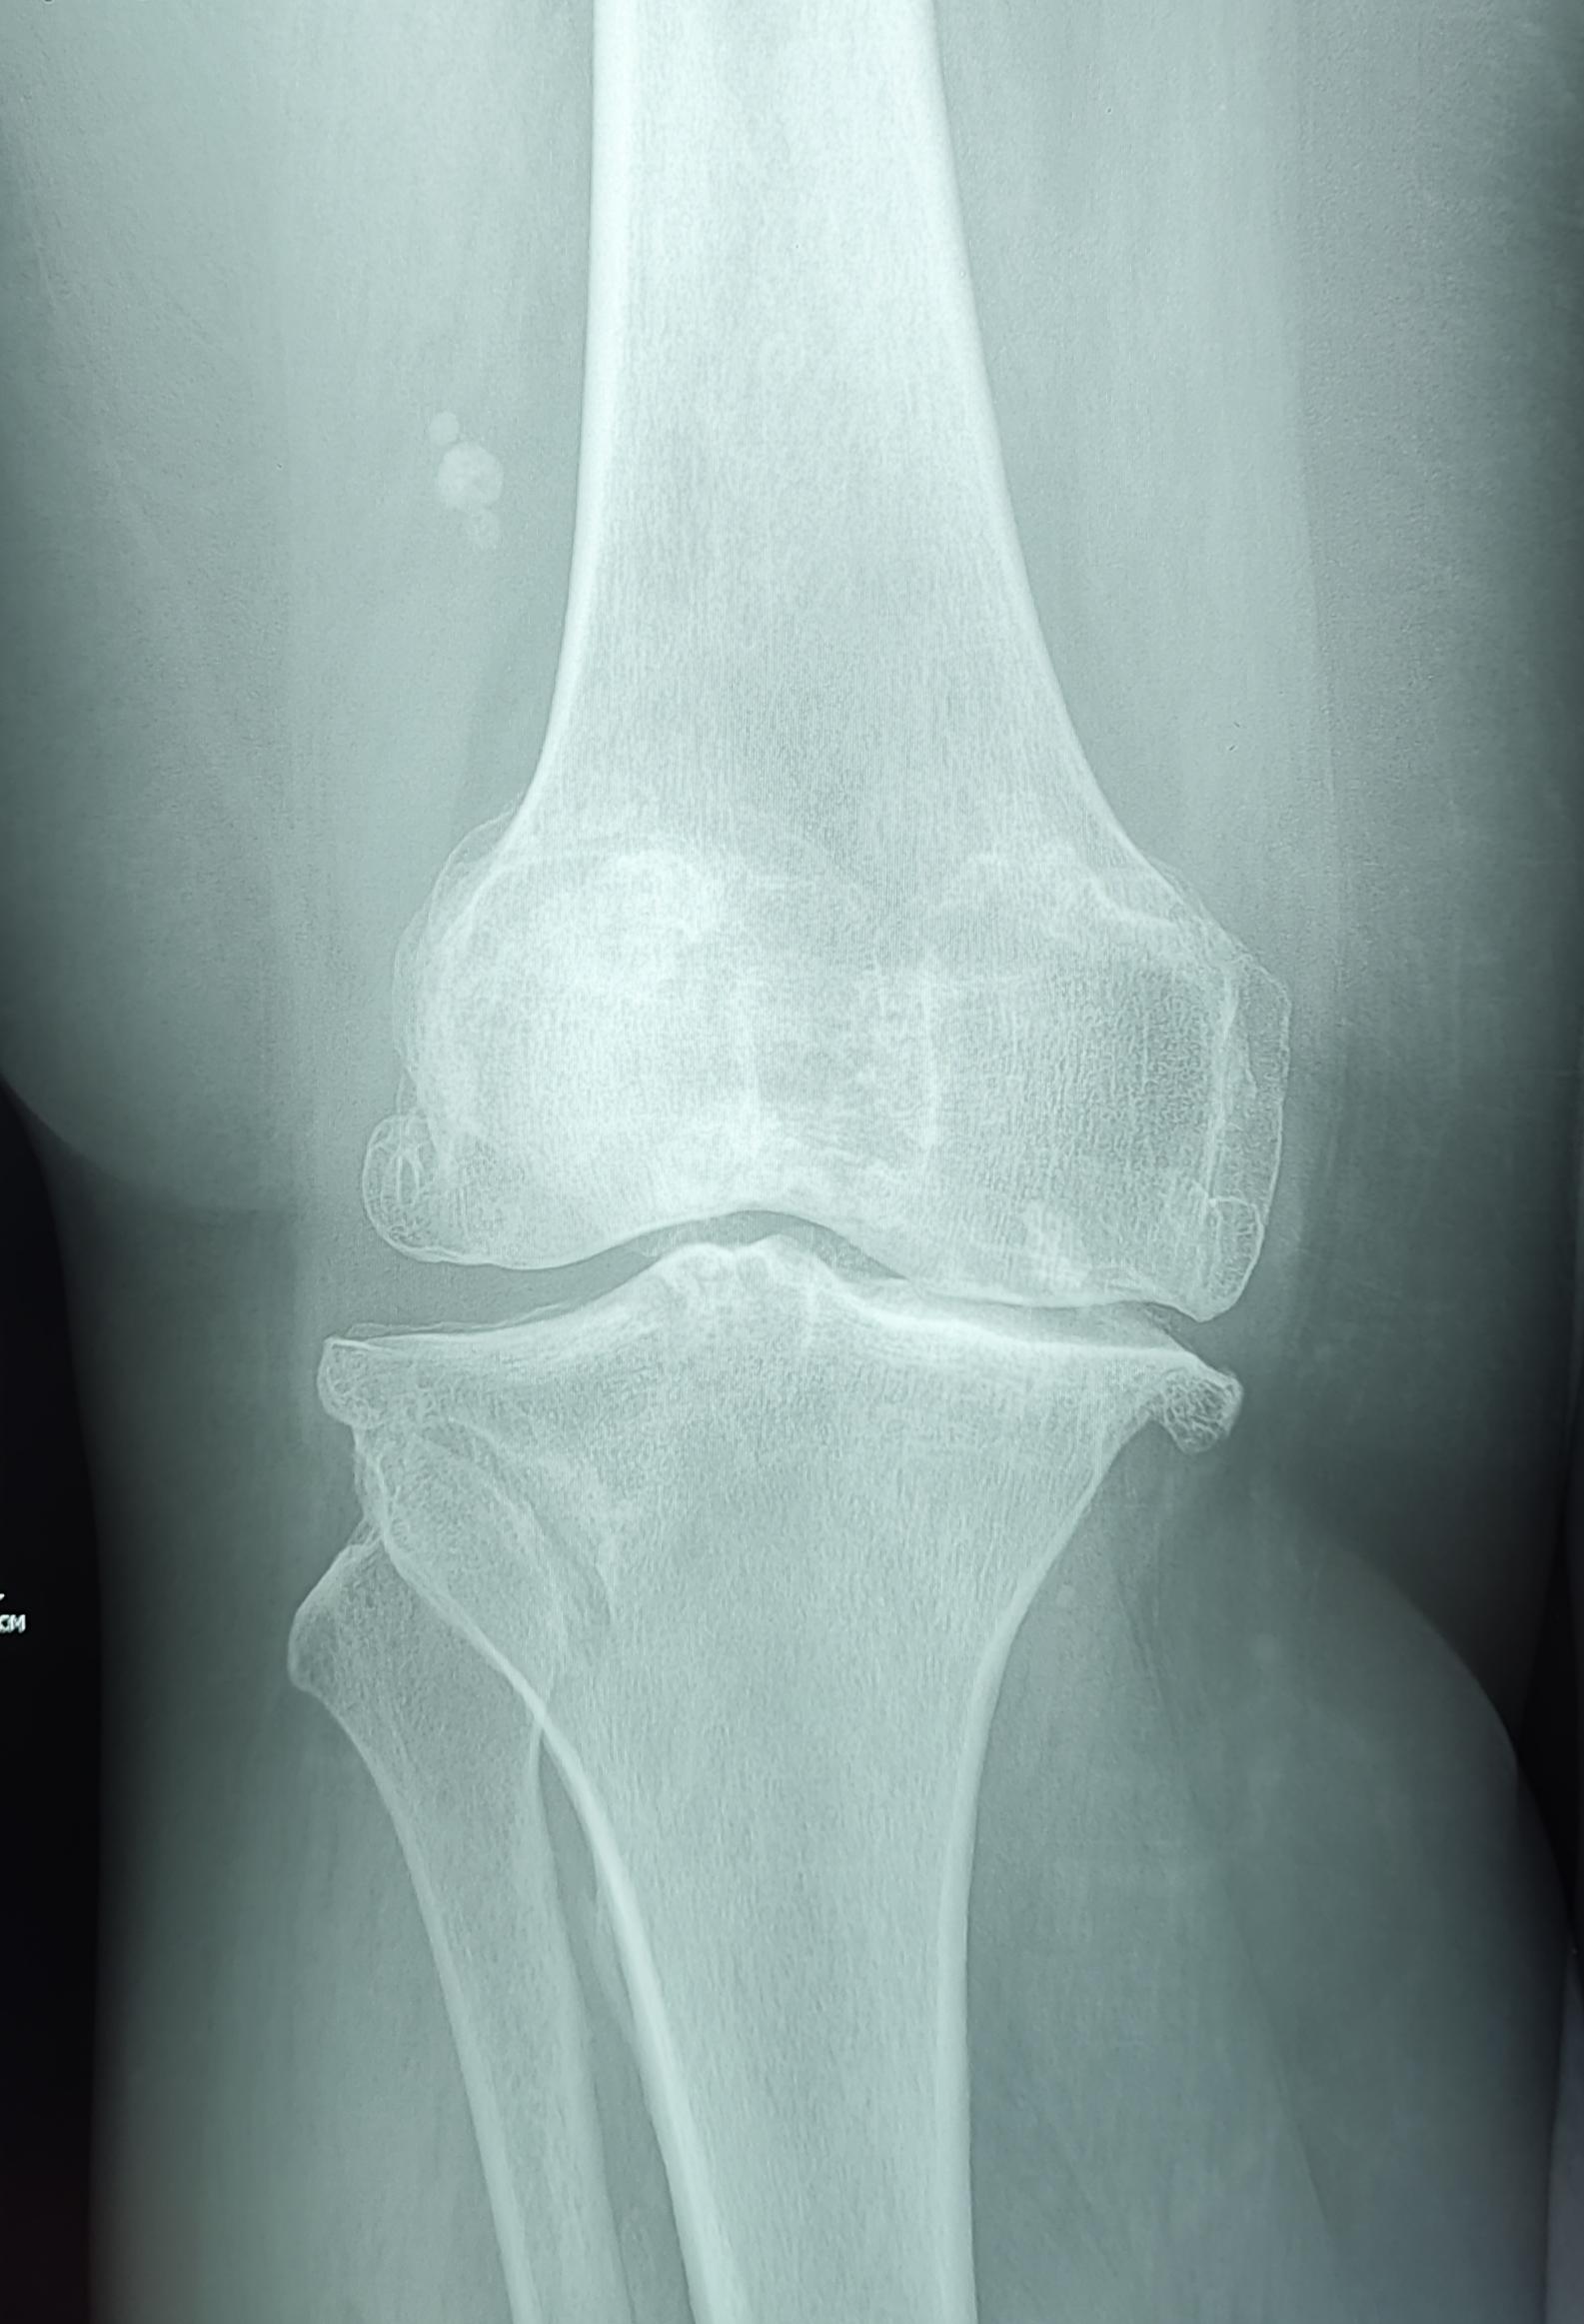

Описание: На Р-граммах правого к/с в 2х проекциях: Значительное сужение суставной щели в медиальных отделах до 1.6 мм, субхондральный склероз, краевые костные разрастания, заострение полюсов надколенника, уплотнение его внутренней поверхности ,по ходу внутренней поверхности синовиальной оболочки визуализируются единичные округлые хондроматозные тела №~7,размером от 5 мм до 25 мм в диаметре. Заключение: Хондроматоз правого коленного сустава. Гонартроз справа 3 ст. по Kellgren.Пателло-феморальный артроз.